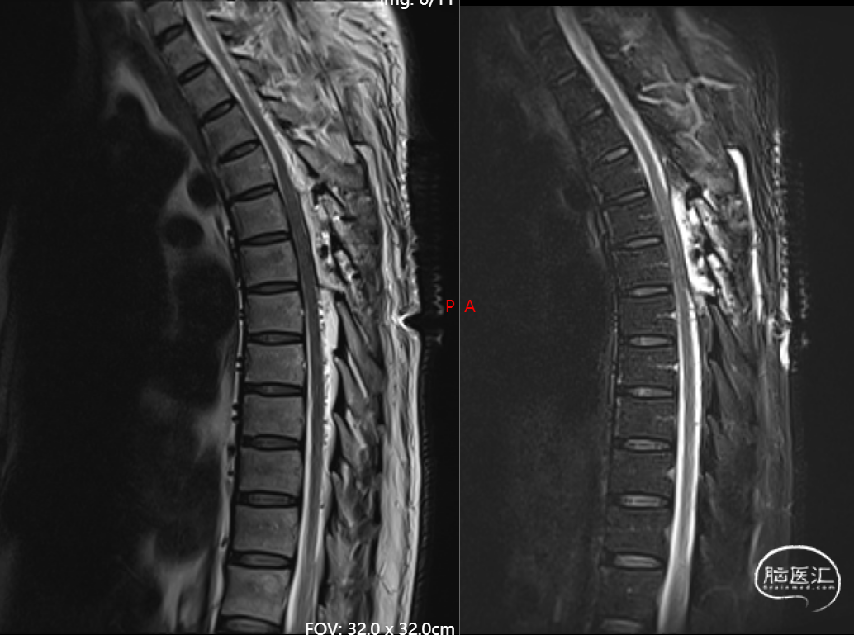

现病史摘要:缘于5月余前患者无明显诱因逐渐出现双下肢无力,走路时酸胀感,易疲劳,不能长距离行走,右下肢明显,晨轻暮重,无疼痛、肌肉萎缩和大小便异常,完善颈胸部MRI显示胸髓表面多发迂曲血管影,胸5-12椎体水平髓内异常信号。

术后4天影像(2024-02-26, 本院)

image.png

· 通过胸腰椎MRI检查大多可见到血管流空影,进一步脊髓血管造影可以明确诊断。

显微镜下探查瘘口多位于神经根附近的硬脊膜上,烧闭并切断瘘口处血管即可,脊髓异常引流静脉会逐渐自动消失,脊髓张力会随之下降。